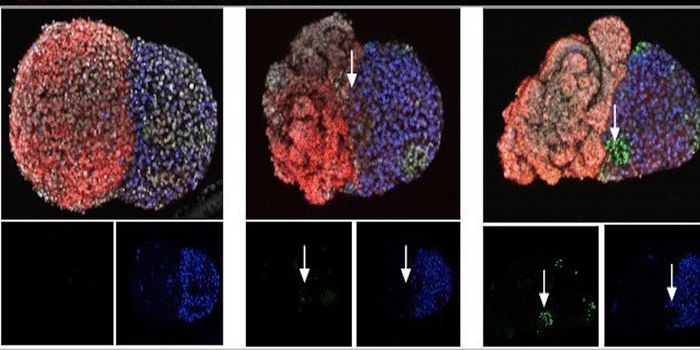

JUN 02, 2016Cell & Molecular BiologyMitochondrial replacement therapy was hailed as a promising new way to overcome diseases passed down in the DNA of mitoc ...